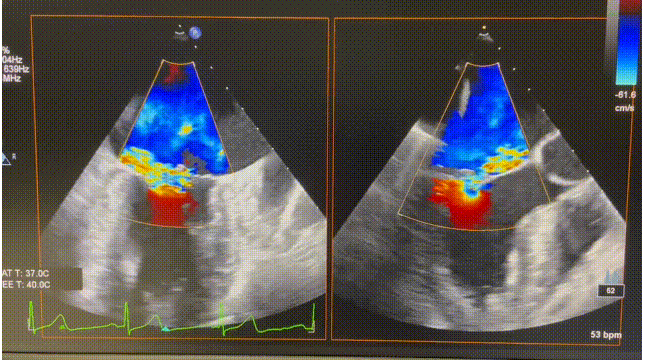

患者为74岁女性。术前心超显示后叶P2脱垂,伴极重度二尖瓣反流(VCW 9mm*16mm),图2。患者全麻后,在超声和射线引导下器械经股静脉穿刺房间隔,通过输送系统送入患者左心房,到达二尖瓣膜反流处,在经食道超声及DSA引导下,术者通过反复评估二尖瓣膜脱垂范围、抓捕位置、反流程度,精准夹合,成功植入1枚ValveClasp瓣膜夹。术后即刻左房压力及V波减低,患者反流从5+减少到1+(图3),跨二尖瓣平均压差3mmHg,肺静脉逆流消失,血流动力学改善明显,手术取得圆满成功。

图2 术前心超图。